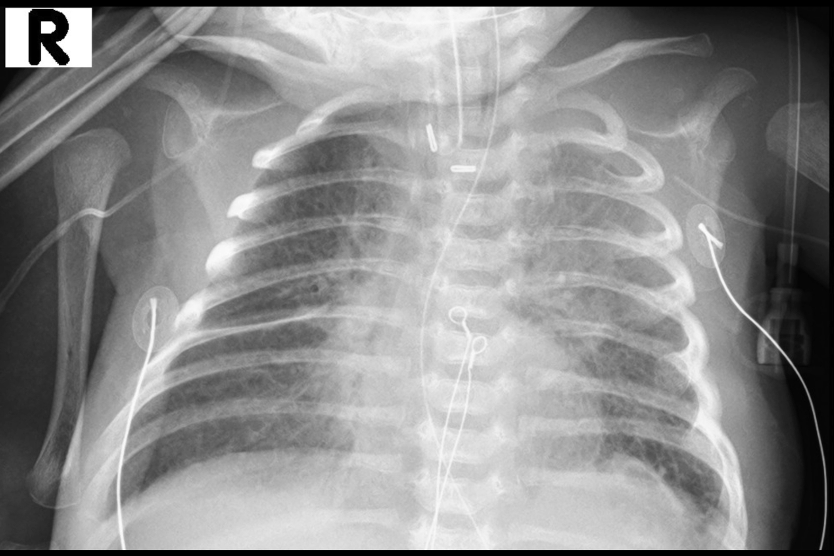

On POD 28, she developed dense collapse/ consolidation of her left lung (figure 1). This was unresponsive to three times daily chest physiotherapy, aided by inhaled hypertonic saline and intra-pulmonary percussion. She was supported with non-invasive ventilation using high flow nasal cannula and nasal bilevel positive airway pressure (BiPAP), prone positioning and antibiotic therapy. On POD 32, it was decided to proceed with bronchosocpy, surfactant instillation and lung insufflation, according to the technique published by Šapina et al., using minor modifications.

Chest radiograph prior to procedure

Figure 1. Chest radiograph prior to procedure.